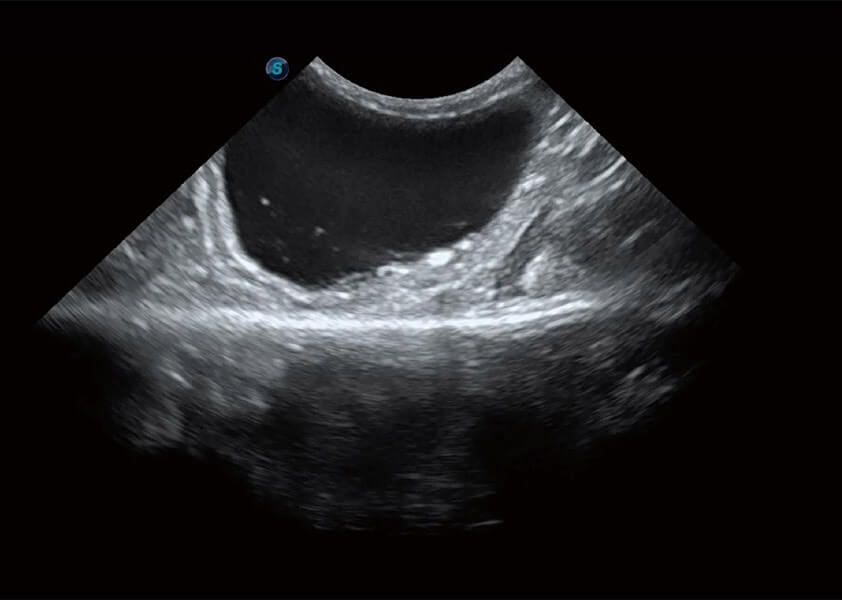

ProPet 60 作为一款高端台式动物超声设备,为动物医生的日常诊断提供了一系列贴合动物临床需求、解决临床实际问题的高级成像功能。凭借全系列高清探头,满足医生对腹部、心脏、生殖、浅表、肌骨等成像的所有需求,切实帮助您提升检查效率,提高诊断信心。

动物是人类最亲密的朋友和最值得信赖的伙伴。银河集团官网也一直致力于探索动物专用的超声影像解决方案。 全新推出的ProPet系列,是银河集团官网在动物超声影像智能化、专业化、精准化的一次跨越式革新。动物不能用言语来表述自己的不适,通过超声影像,ProPet系列搭建了动物医生与不同物种沟通的“桥梁”,为动物医生注入了“治愈之力”。